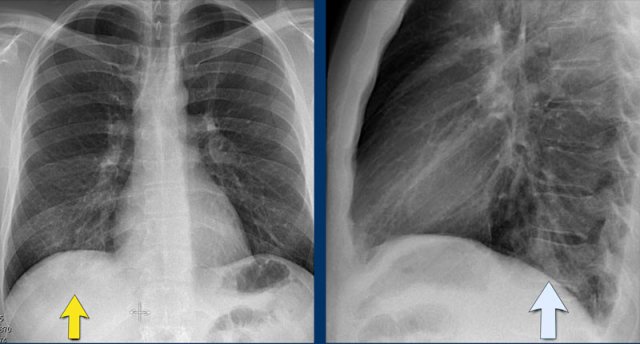

The PA-film shows a silhouette sign of the left heart border.

Even without looking at the lateral film, we know, that the pathology must be located anteriorly in the left lung.

This was a consolidation due to a pneumonia caused by Streptococcus pneumoniae.

Here a consolidation which is located in the left lower lobe (yellow arrow).

Notice that there is a normal silhouette of the left heart border (blue arrow).

The absence of a silhouette sign tells us that the pathology is located in the left lower lobe and not in the lingula.